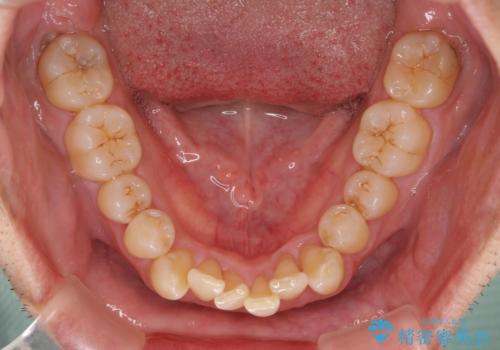

担当医としてはもう少し前歯のデコボコを改善したいところでしたが、患者様としては十分に満足いく歯列であり、マウスピース矯正に飽きてしまったとのことで、治療終了となりました。